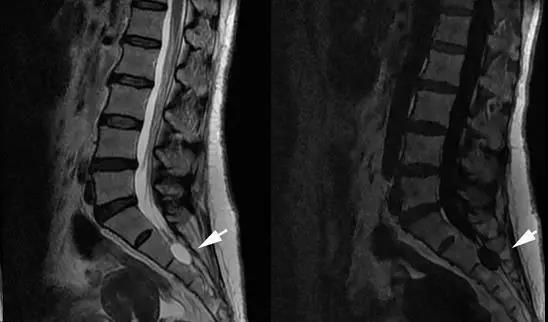

图:常规磁共振

然而,治疗有个难点,就是术前根据常规磁共振影像,难以判别骶管囊肿与马尾神经根的解剖关系,特别是很难预判骶管囊肿漏口的准确位置,这些信息都要在手术台上才能最终明确。